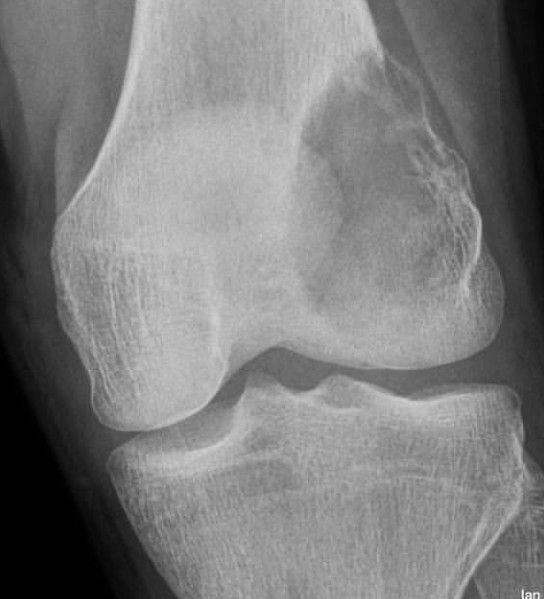

OSSEOUS METASTASES: š“ can appear non-aggressive or aggressive š“ lung cancer most common primary overall š“ breast cancer in women, often osteoblastic metastases š“ prostate in men most common cause of osteoblastic metastases š“ distribution matches red marrow, rare beyond elbow and knees š“ fractures that should make you think underlying lesion such as metastasis: -- subtrochanteric femur or humerus transverse fracture -- lesser trochanter avulsion fracture in adult š“ beware diffuse increased bone density in extensive osteosclerotic metastases - easy to miss š“ expansile "blow out" lytic metastases; think renal cell carcinoma or thyroid carcinoma š“ absent pedicle "winking owl sign" on frontal spine radiographs in lytic posterior element involvement.